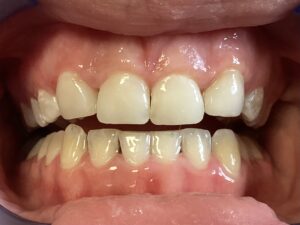

This patient arrived at my practice last week with 2 congenitally missing laterals incisors. Her orthodontist moved the canines into the position of the lateral incisors to fill the gaps but canines don’t look like incisors. They are pointy and “fat” so I told them upfront that although perfect aesthetics will not be achieved we can greatly improve the look and also remove the decay. The procedure required a single 2hr appointment and a very pleasing result was achieved with a very happy teenager leaving the practice that day. Further improvements can be done at a next visit by removing the white spots on the first premolars.